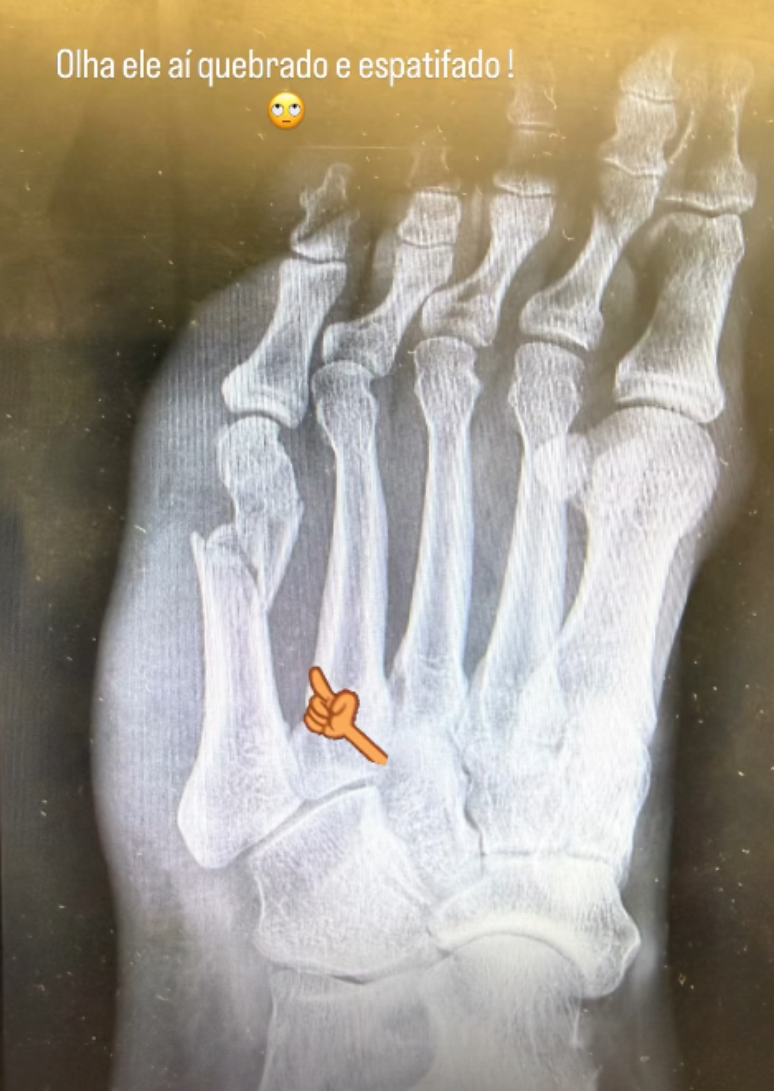

Flávia Monteiro passou por um susto após sofrer um acidente dentro de casa.

A atriz precisou ser internada no Rio de Janeiro depois de quebrar o pé ao cair durante uma brincadeira com a filha.

Segundo relato, o momento aconteceu quando ela interagia com a criança e foi surpreendida pela agitação do cachorro da família.

Com a queda, ela fraturou o quinto metatarso e precisará passar por cirurgia.